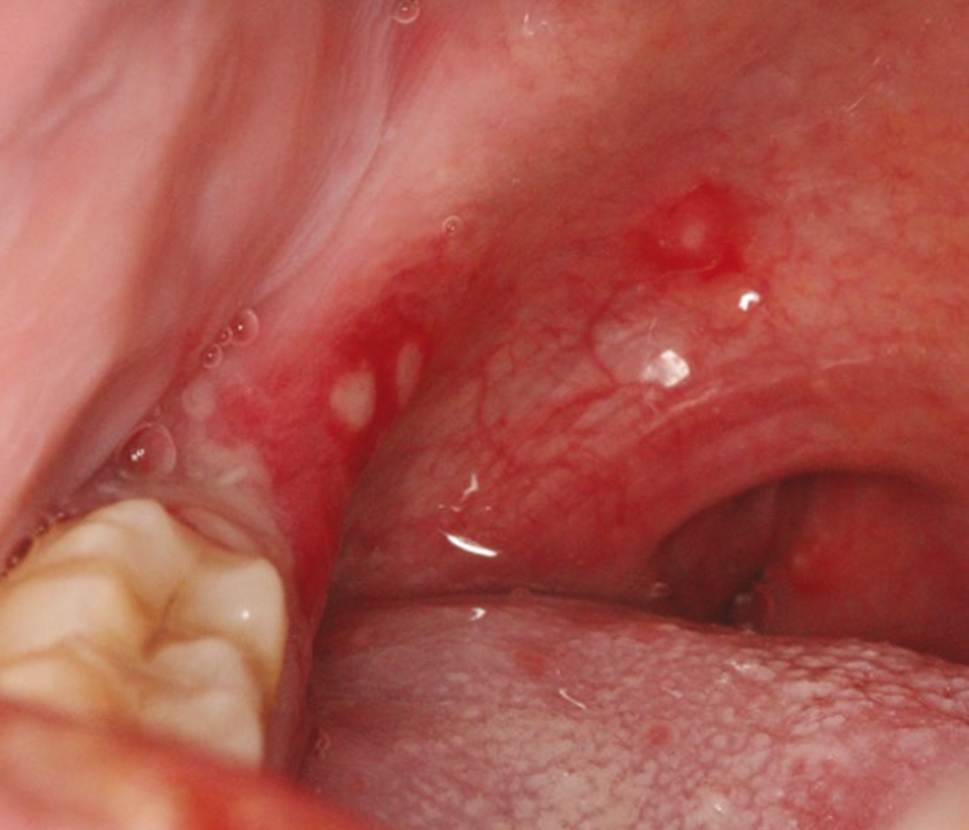

ჰერპანგინა

პირის ღრუს დათვალიერებით ვლინდება ყელის ჰიპერემია და ყვითელი- მონაცრისფრო-მოთეთრო პაპულოვეზიკულური გამონაყარი. დაზიანება უხშირესად ვრცელდება რბილი სასის თაღზე, რბილ სასაზე, ტონზილებზე და ნაქზე. ძალიან ხშირად დაზიანება შეიძლება იყოს მაგარ სასაზე, ენაზე და ლოყის ლორწოვანზე. მორფოლოგიური ელემენტების რაოდენობა ვარირებს და როგორც წესი 10 ზე ნაკლებია. თავდაპირველად ჩნდება პაპულები, რომელიც 24 საათში გარდაიქმნება ვეზიკულებად. ვეზიკულების დიამეტრი ჩვეულებრივ 1-2 მმ-ია და გარშემორტყმულია ერითემის არეოლით. დაახლოებით 24 საათის შემდეგ ვეზიკულების გასკდომის შედეგად წარმოიქმნება 3-4 მმ დიამეტრის ზედაპირული ყვითელი ნაცრისფერი წყლულები, ინტენსიური ერითემული რგოლით (სურათი 7).

სურათი 7

ჰერპანგინას დიაგნოზი ასევე კლინიკურია და ისმება ორალური ენენთემის ტიპიური გარეგნობისა და ადგილმდებარეობის საფუძველზე ( 10- ზე ნაკლები ჰიპერემიული ყვითელი, მორუხო, თეთრი პაპულოვეზიკულური გამონაყარი რბილი სასის თაღზე, რბილ სასაზე, ტონზილებზე და ნაქზე) ,რომელსაც თან ახლავს მაღალი ცხელება.